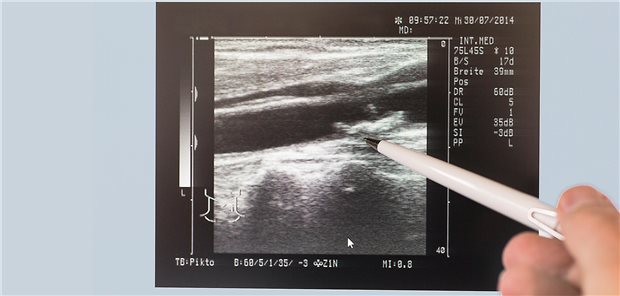

Empfehlungen eines Gefäßmediziners

Welche Patienten mit asymptomatischer Carotis-Stenose operiert werden sollten